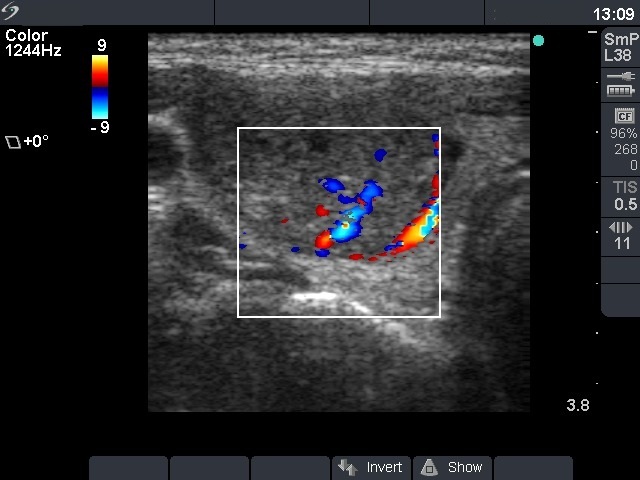

Ultrasonography: the thyroids were echonormal. There was a moderately hypoechogenic nodule displaying both perinodular and intranodular blood flow.